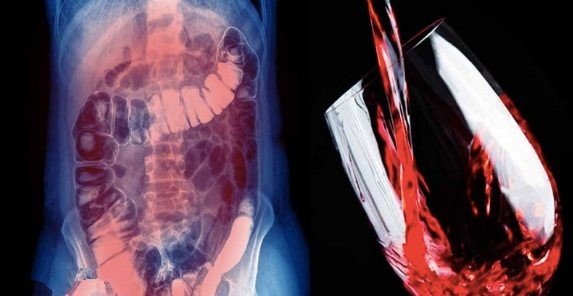

The journal Addiction published research that provided significant evidence that alcohol is commonly associated with cancers of the rectum, liver, colon, esophagus, oropharynx (part of the pharynx in the mouth), larynx and, in women, the breast.

Colon cancer is also linked to alcohol consumption. A study published in the journal Cancer found that every seventh person diagnosed with colon cancer was under 50 years old.

The research clearly confirmed the association between colon cancer and alcohol consumption. The International Agency for Research on Cancer (IARC) in 1988 classified alcohol as a Group 1 carcinogen.

In cases associated with alcohol consumption, colorectal cancer was the most frequently represented.